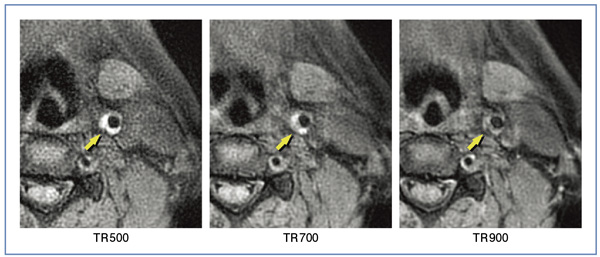

図1は,SE法によるT1強調画像のプラークイメージングである。TRが延長するに従い,驚くほどコントラストが低下することがわかる。心電図同期がいかにコントラストを損なう原因となっているかが理解できる。

図1 TRの違いによるMRプラークイメージングの比較(SE法T1強調画像)